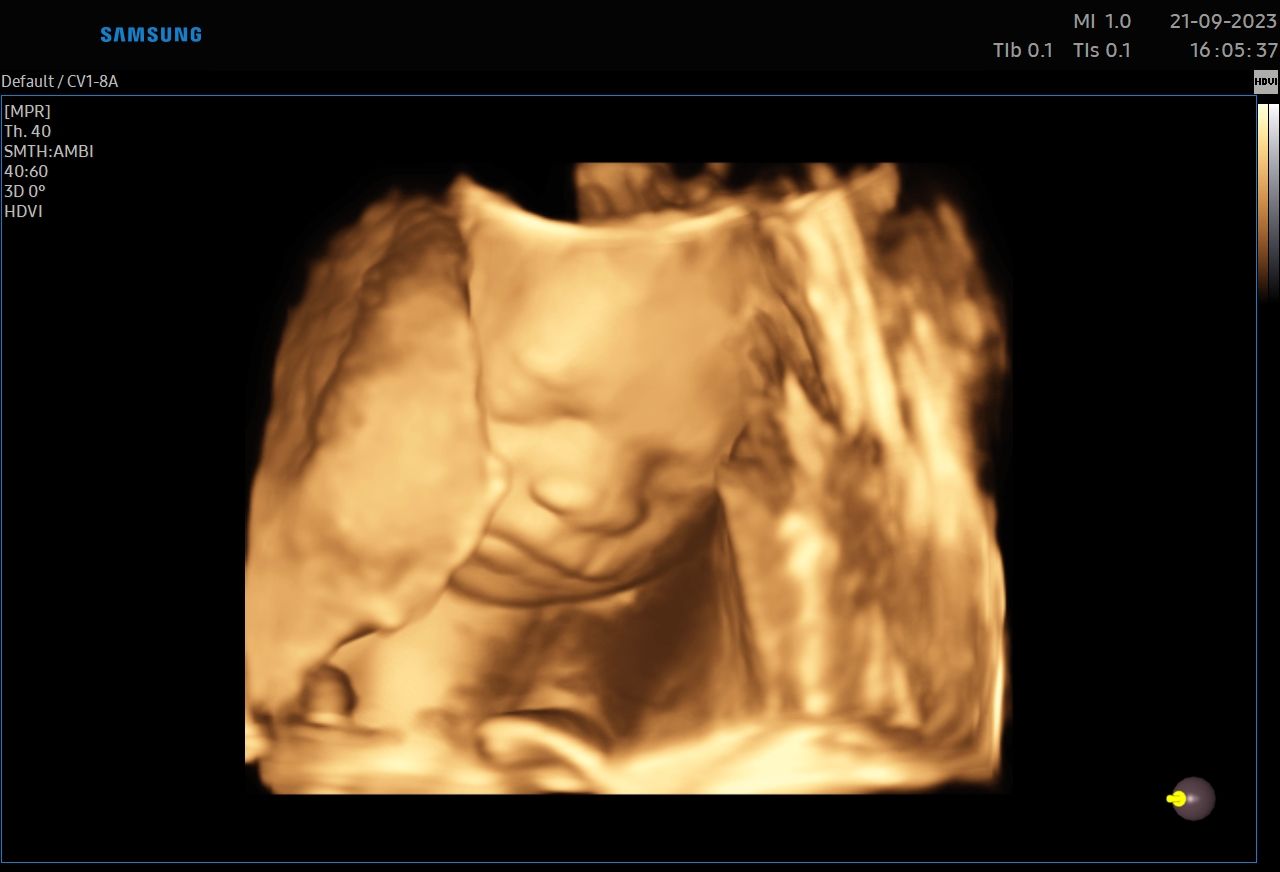

:-) Jestem lekarzem specjalistą w zakresie ginekologii i położnictwa , w ramach prowadzonej praktyki ginekologicznej staram się świadczyć kompleksowe porady lekarskie najwyższym poziomie ,w oparciu o najwyższe standardy jak i przy pomocy najnowszego sprzętu medycznego. W trakcie pracy zawodowej uzyskałem kolejno tytuły specjalisty I stopnia , a później specjalisty II stopnia , a także uzyskałem dodatkowe uprawnienia

CERTYFIKAT BADAŃ PRENATALNYCH POLSKIEGO TOWARZYSTWA GINEKOLOGÓW I POŁOŻNIKÓW

CERTYFIKAT BADAŃ PRENATALNYCH FMF ( FETAL MEDICINE FOUNDATION - LONDYN )

W ramach praktyki wykonuję pełen zakres badań ultrasonograficznych w zakresie ginekologii jak i położnictwa wraz z badaniami prenatalnymi , badaniami ultrasonograficznymi piersi .

Zdjęcia i filmy